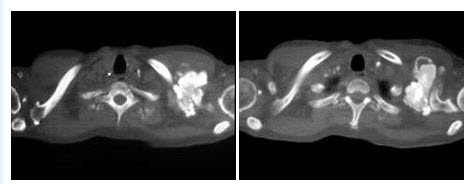

24、多项选择题

男,65岁,左侧腰背部胀痛伴无痛性全程血尿3月余,CT平扫及增强检查如图所示,下列说法正确的是()

A.平扫时见左肾上极有一软组织肿块影,其边界较清楚

B.增强扫描肾皮质期可见肿块明显强化,其内亦有无强化区

C.增强扫描肾实质期可见肿块强化迅速下降,但密度比平扫时仍要高

D.考虑为左侧肾癌

E.考虑为左侧肾错构瘤